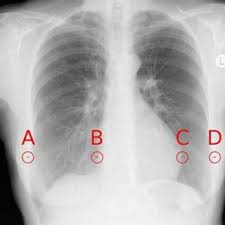

Chestx Ray8 Hospital Scale Chest X Ray Database And Benchmarks On Weakly Supervised Classification And Localization Of Common Thorax Diseases Arxiv Vanity